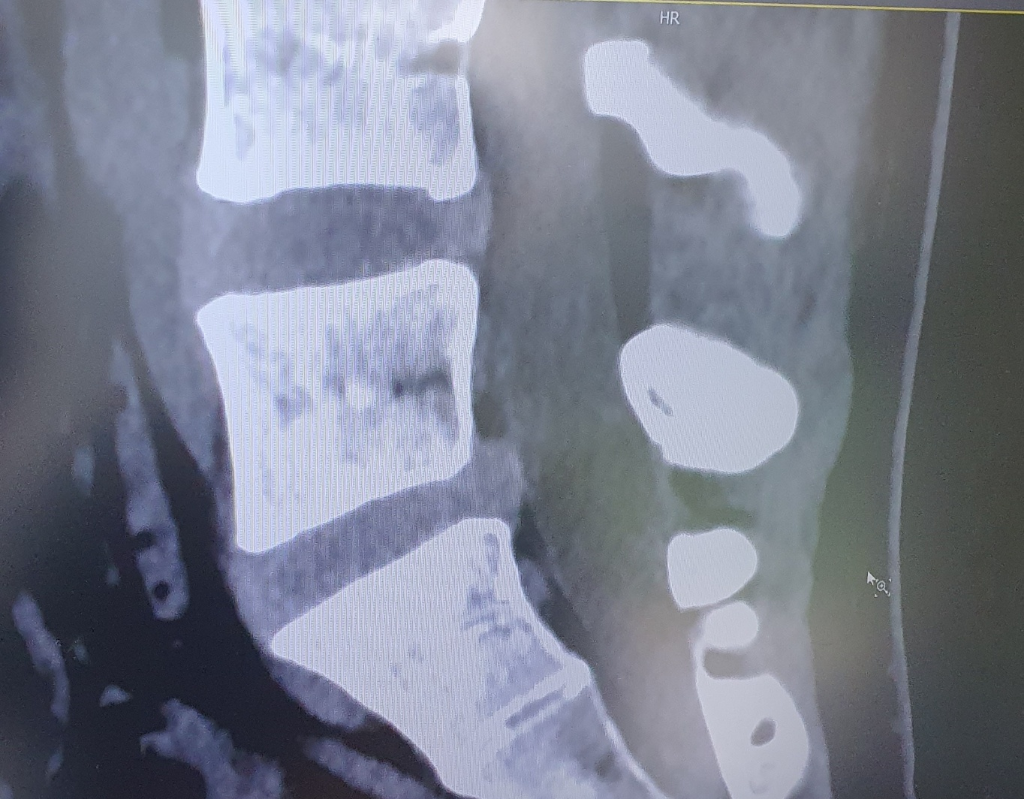

통증이 지속된다면 신경 차단 주사 치료를 시행해 보시는 것도 좋습니다. 디스크가 돌출되어 주변 신경을 자극하면서 허리 통증 및 하지 저림, 방사통, 근력 저하 등 증상들이 나타날수 있는데 신경 차단 주사 치료가 증상 완화에 도움이 됩니다.